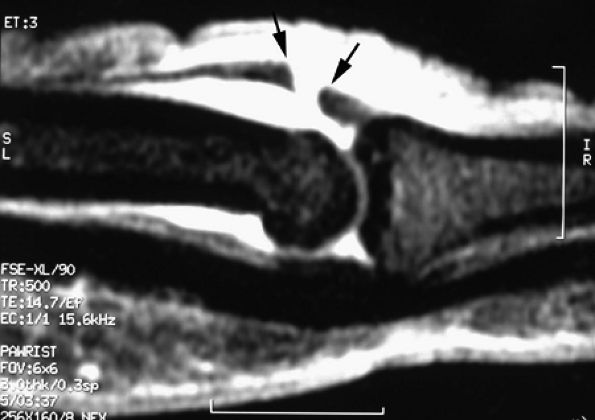

The UCL lies deep to the overlying low-signal adductor aponeurosis on coronal images (Figs. 11.7 and Fig. 11.8). In a nondisplaced partial or complete tear of the UCL, the ligament appears thickened all along its course, sometimes with a small gap. When displaced, the UCL appears as a proximally retracted round or stump-like structure, which demonstrates low signal on all sequences. It is no longer parallel to the long axis of the thumb and presents an increased horizontal orientation.

Stener's lesion may present with a “yo-yo on a string” pattern, with the retracted and balled-up UCL representing the yo-yo and the more distal linear adductor aponeurosis representing the string (Fig. 11.9).

On axial images, the ligament may be seen lying above or intersecting the adductor aponeurosis.